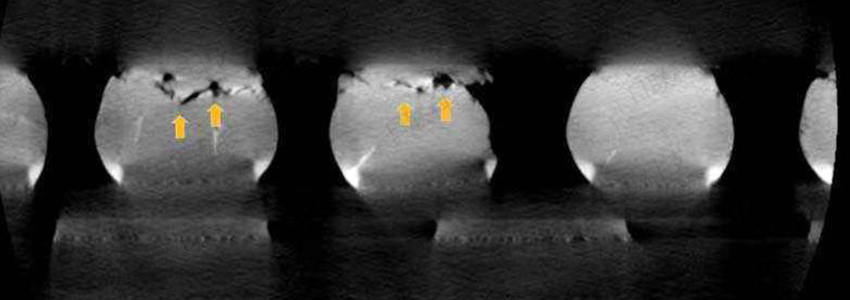

常用的X射线无损检测设备还有X射线检测仪,它可适用于BGA检测,PCB板焊接检测,电池检测,封装检测,电子元器件检测,精密铸件裂缝,焊接,金属材料部内缺陷,精密器件等物品的内部检测。